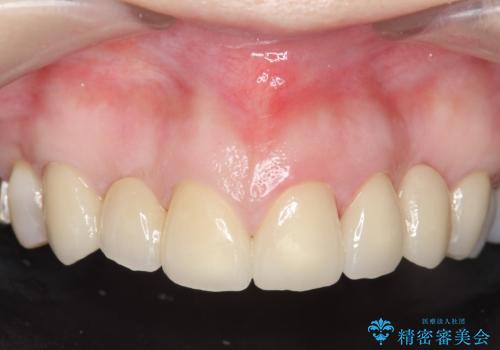

- 昔治療した前歯の被せ物の見た目を改善したいといらっしゃった方の症例です。

左上4番目の歯から右上3番目の歯まで計7歯のクラウンを除去し、オールセラミッククラウンによる補綴を行いました。

今回用いたオールセラミッククラウンはジルコニアフレームという白い素材の上にセラミックを盛っているため、審美性が非常に高いのが特徴です。